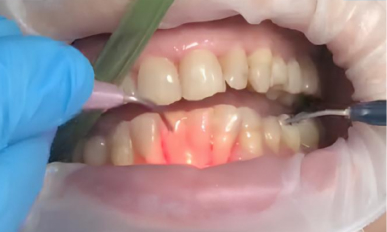

2. Лазерная обработка: Диодный лазер Medency Primo Triplo был настроен на длину волны 635 нм в режиме «периодонтит», с пародонтологической насадкой 400 мкм. Лазерный луч осторожно направляли на воспаленные ткани пародонтальных карманов для удаления бактериального налёта, стимуляции заживления и уменьшения глубины карманов.

3. Дезинфекция: После лазерной обработки область лечения тщательно промыли антисептическим раствором для удаления остатков бактерий и воспалённых тканей.